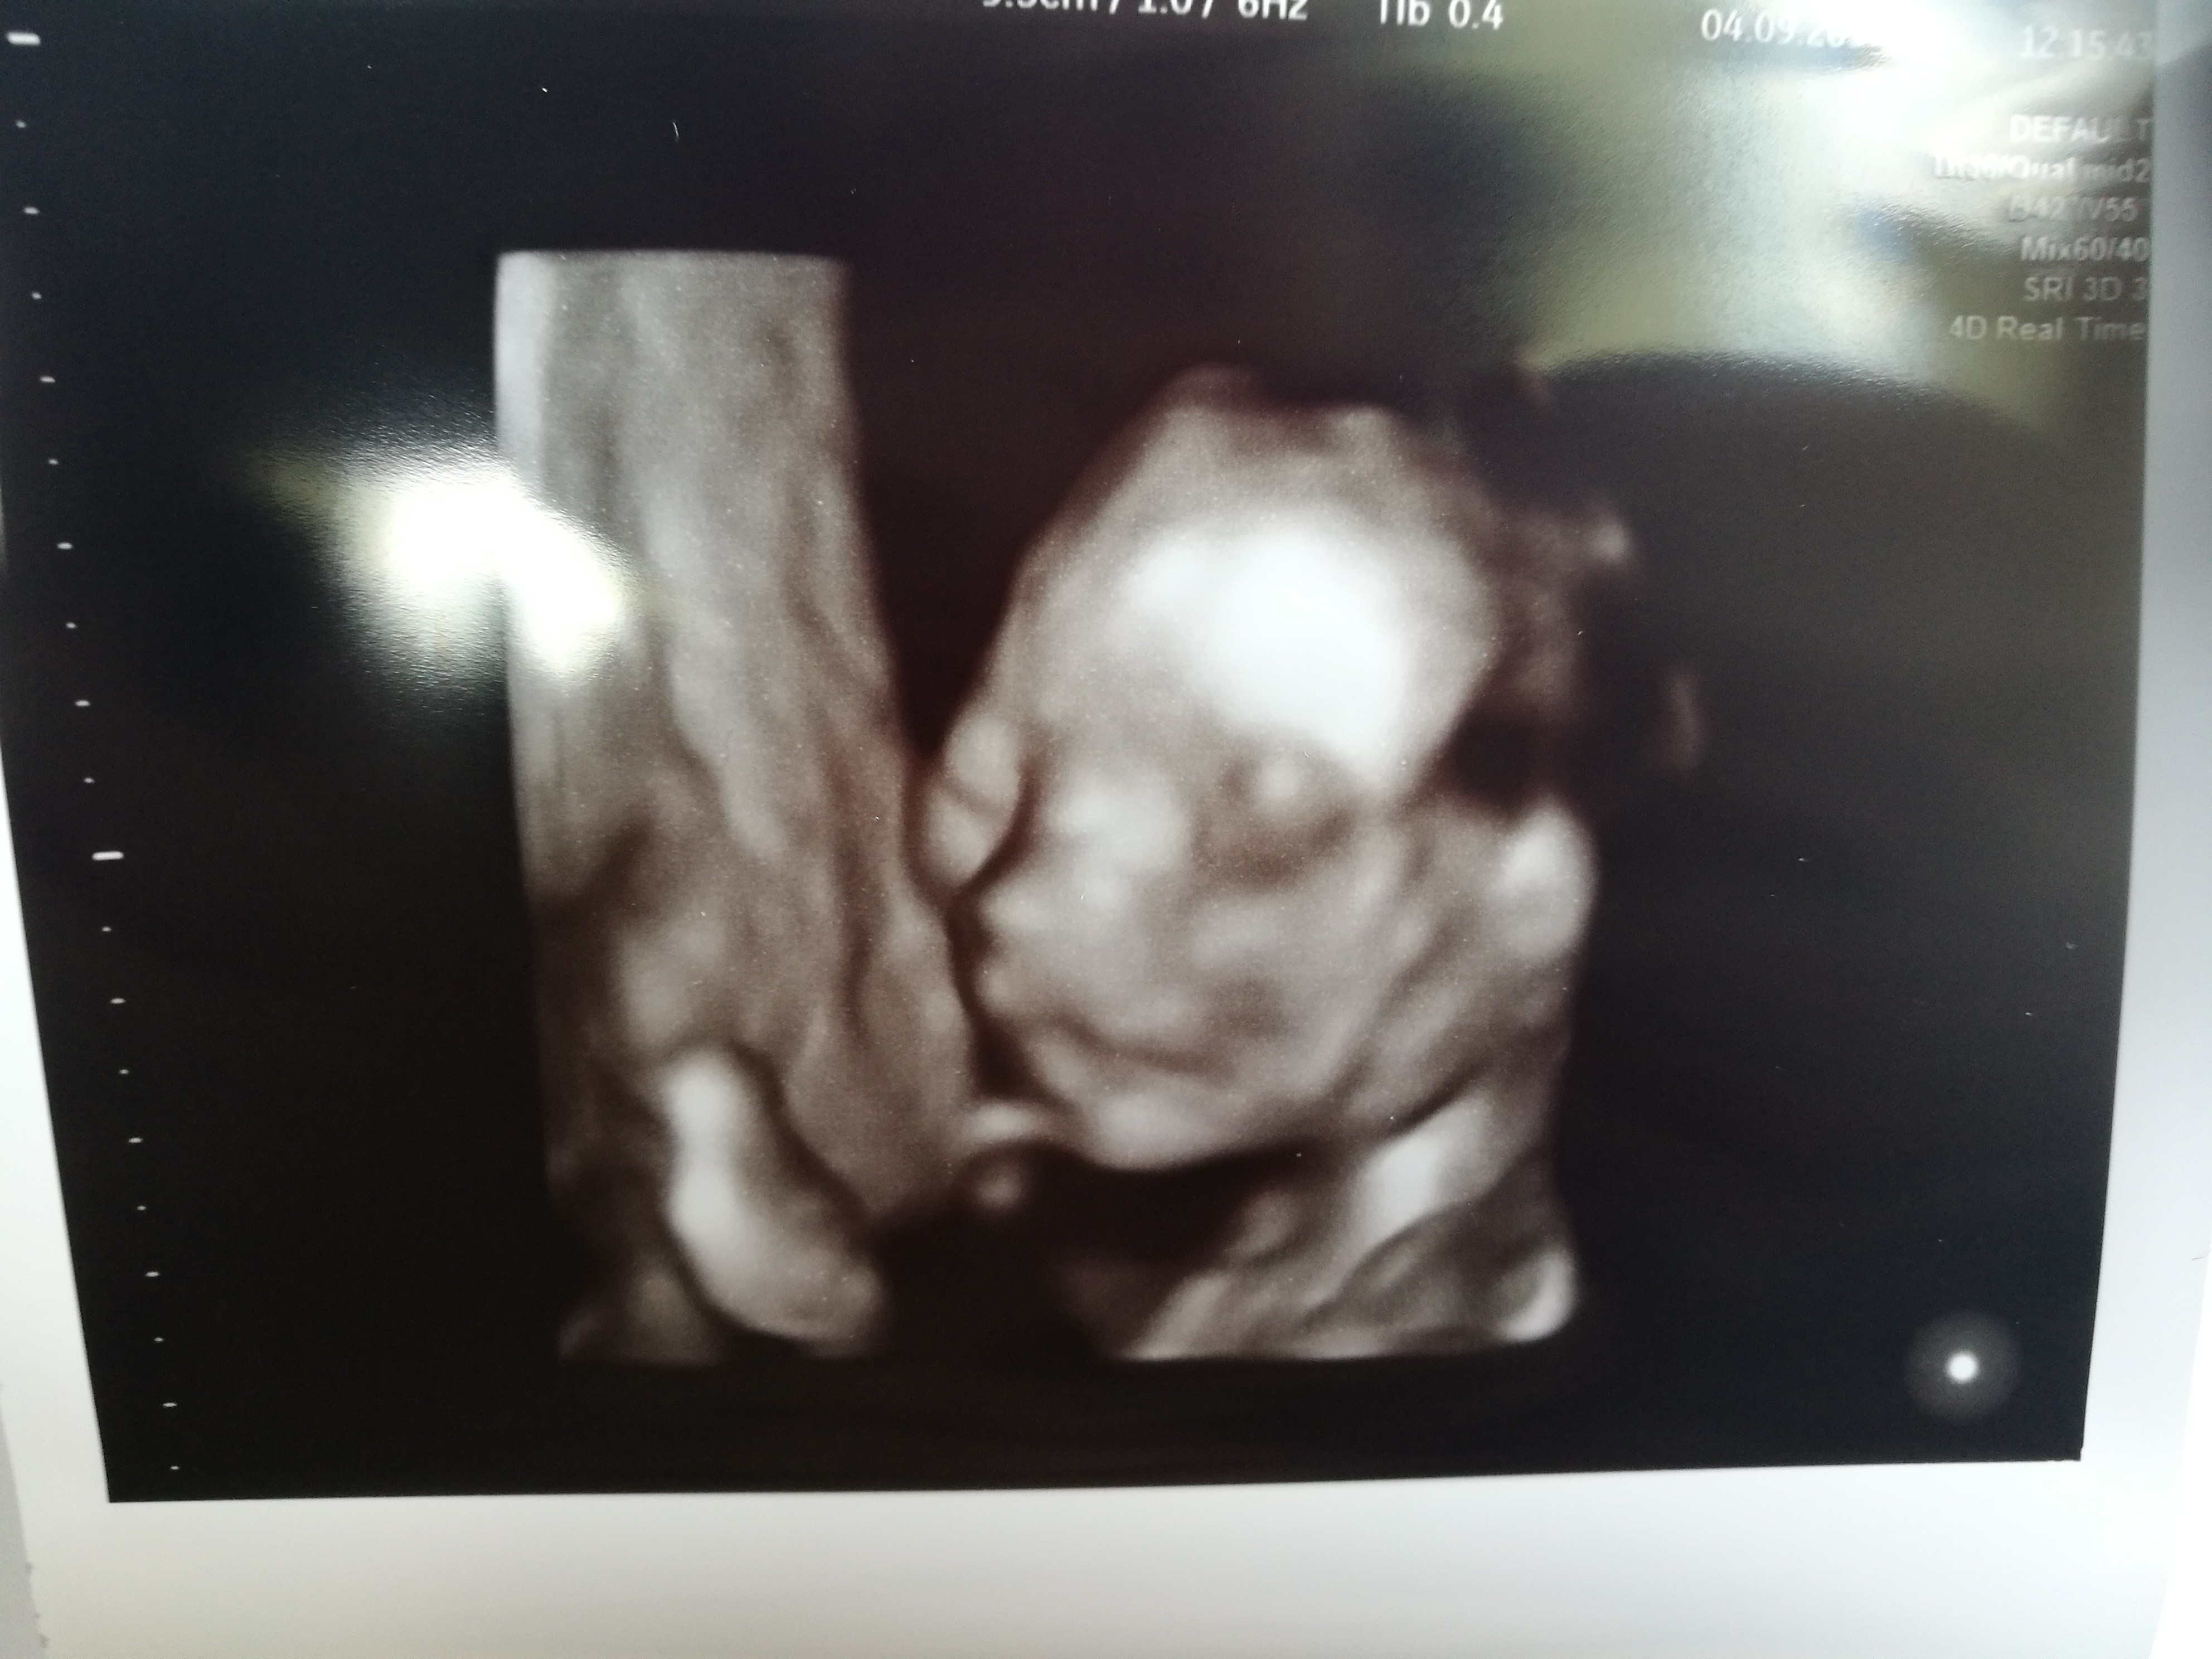

Ale duży, gratuluję. W którym tygodniu Jesteś?My juz po połówkowych 502g chłopaka![]()